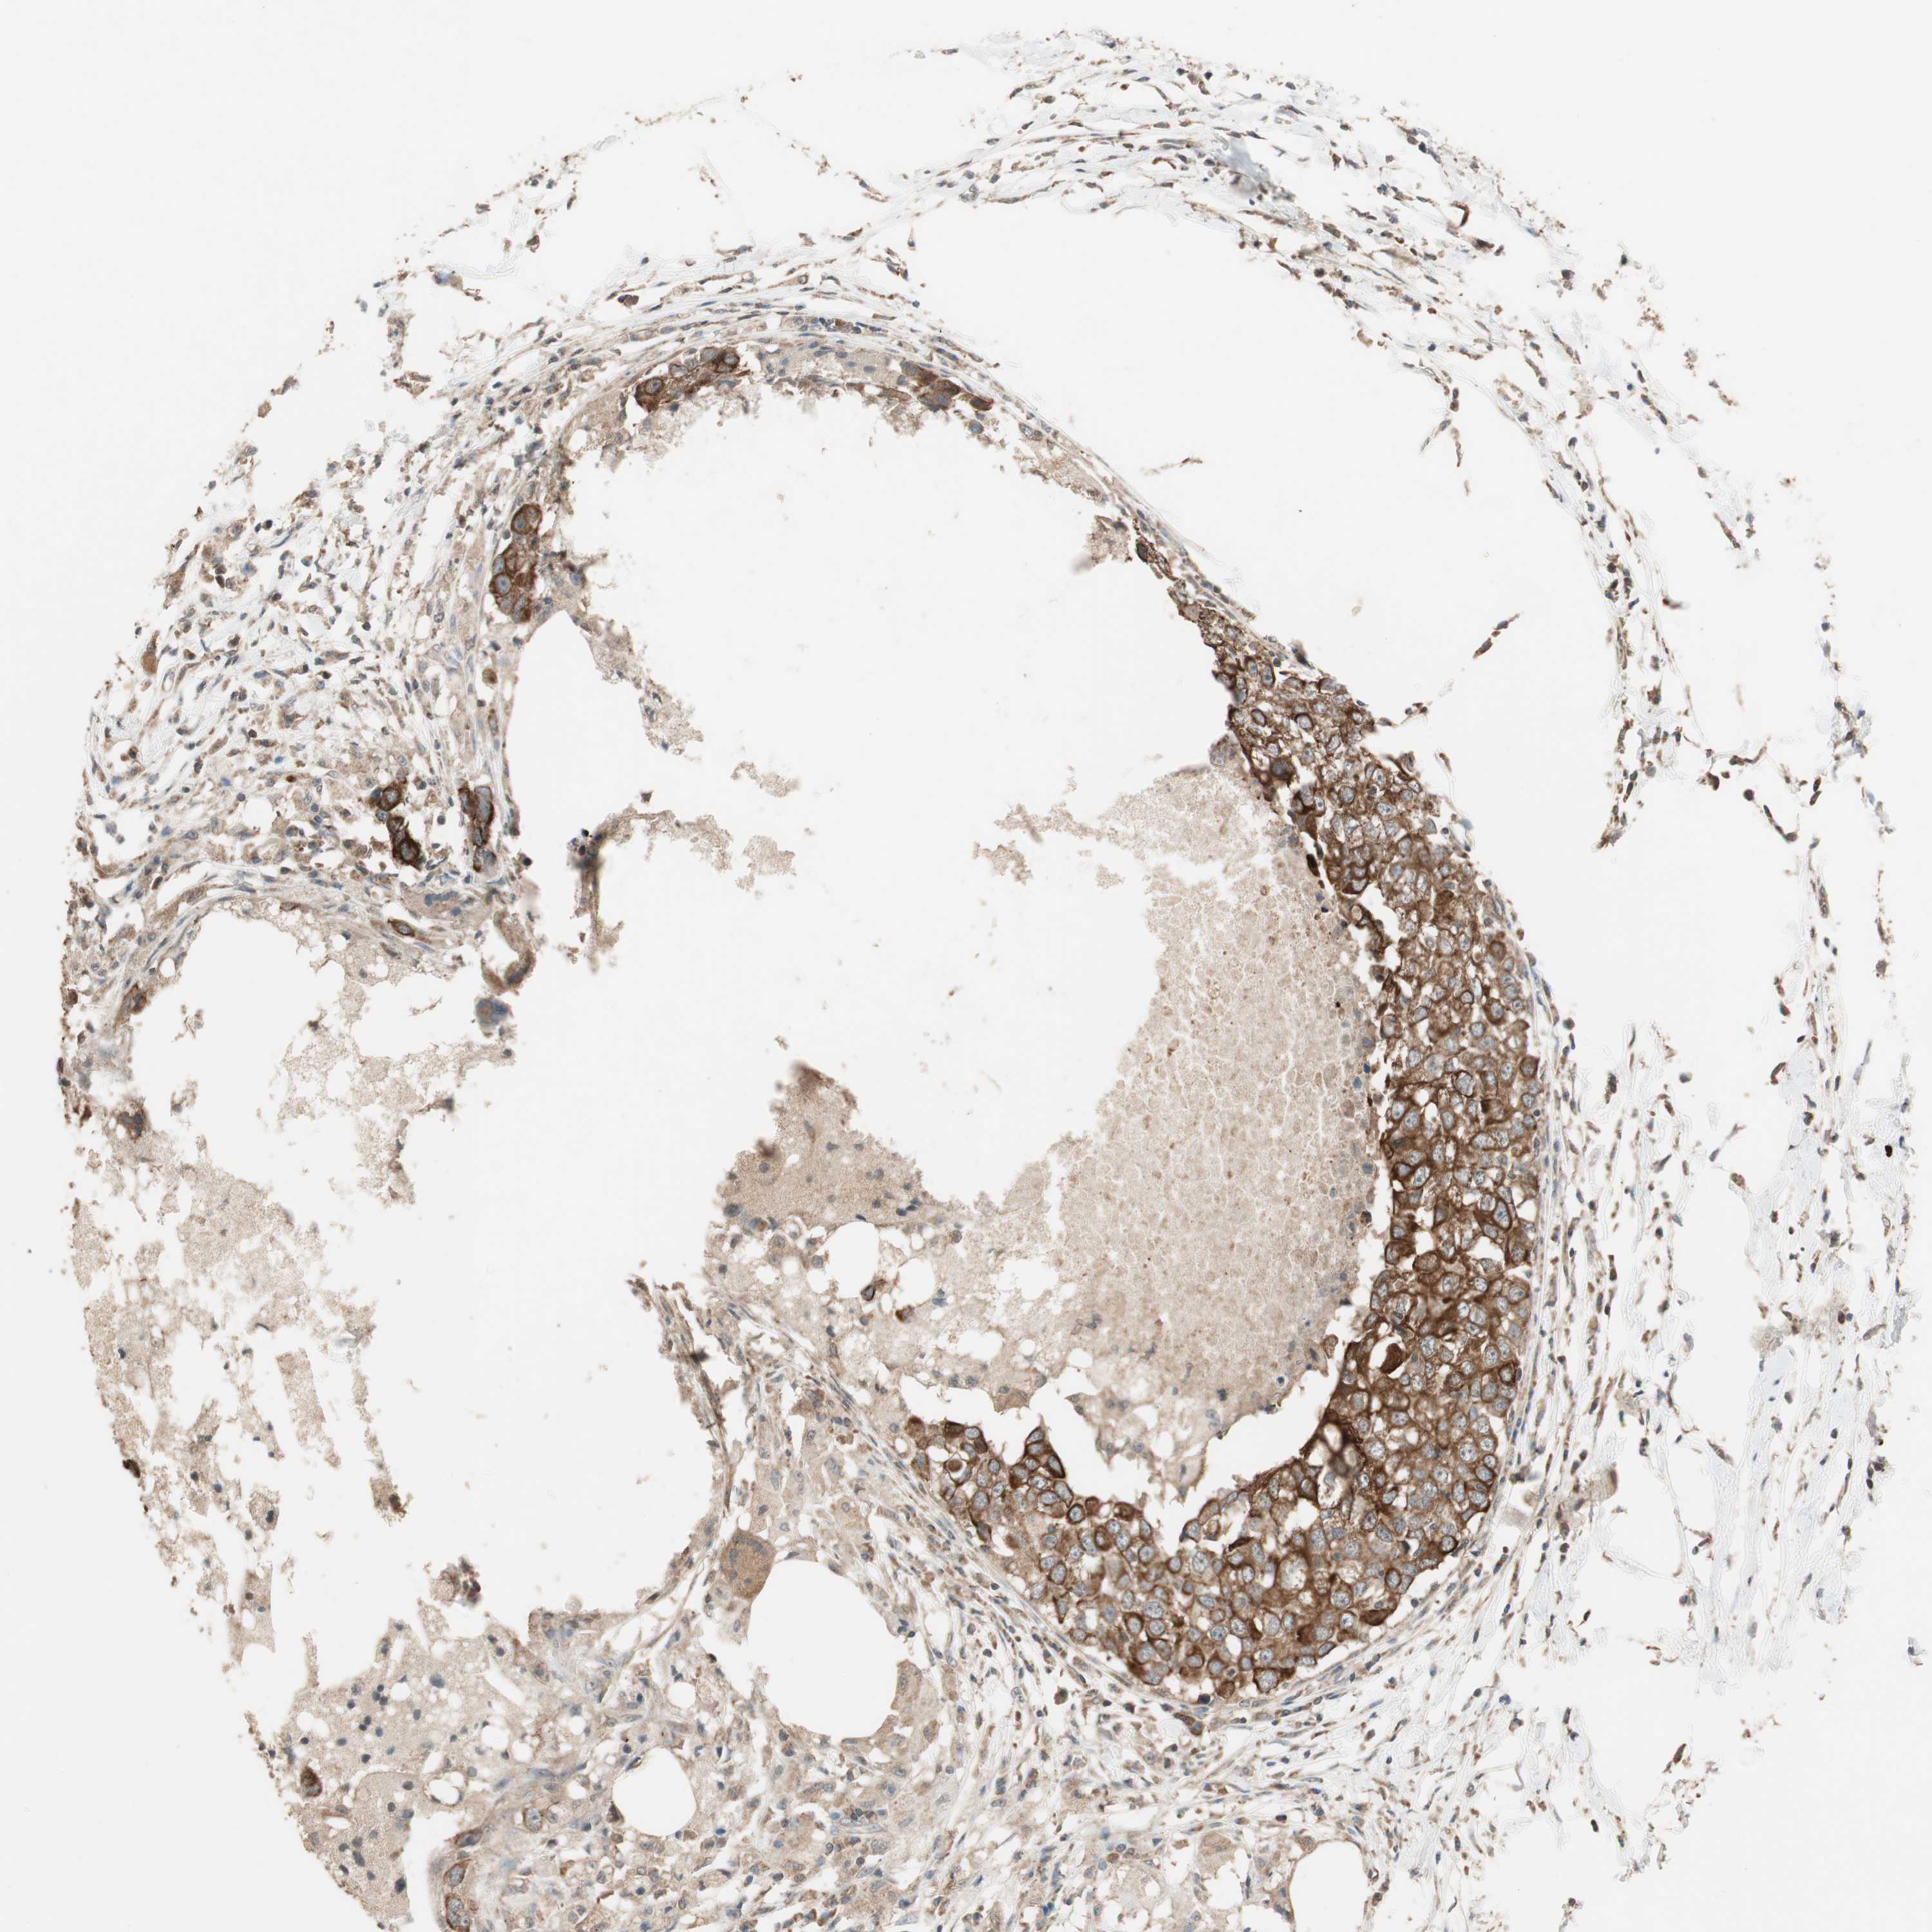

CANCER BREAST CANCER Show tissue menu

BRCA TCGA BRCA VALIDATION PROTEIN EXPRESSION